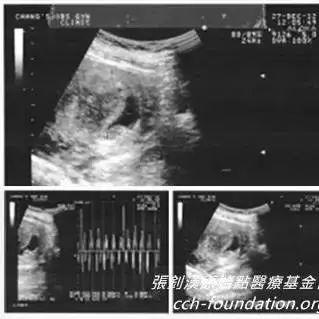

學員原始點應用與處理過程:我是原始點臺北志工2014年2月間一個晚上上完廁所發現自己血尿了當下就用兩斤多的生姜切片用1000c.c.的水熬煮成300c.c.的濃姜湯喝完不久就不再血尿了第二天起床 小腹部很不舒服有時劇痛 有時陣痛劇痛時手腳都是冰冷的就這樣來來回回十多分鐘之后就不再痛了所以我也不在意過了一星期血尿又來...